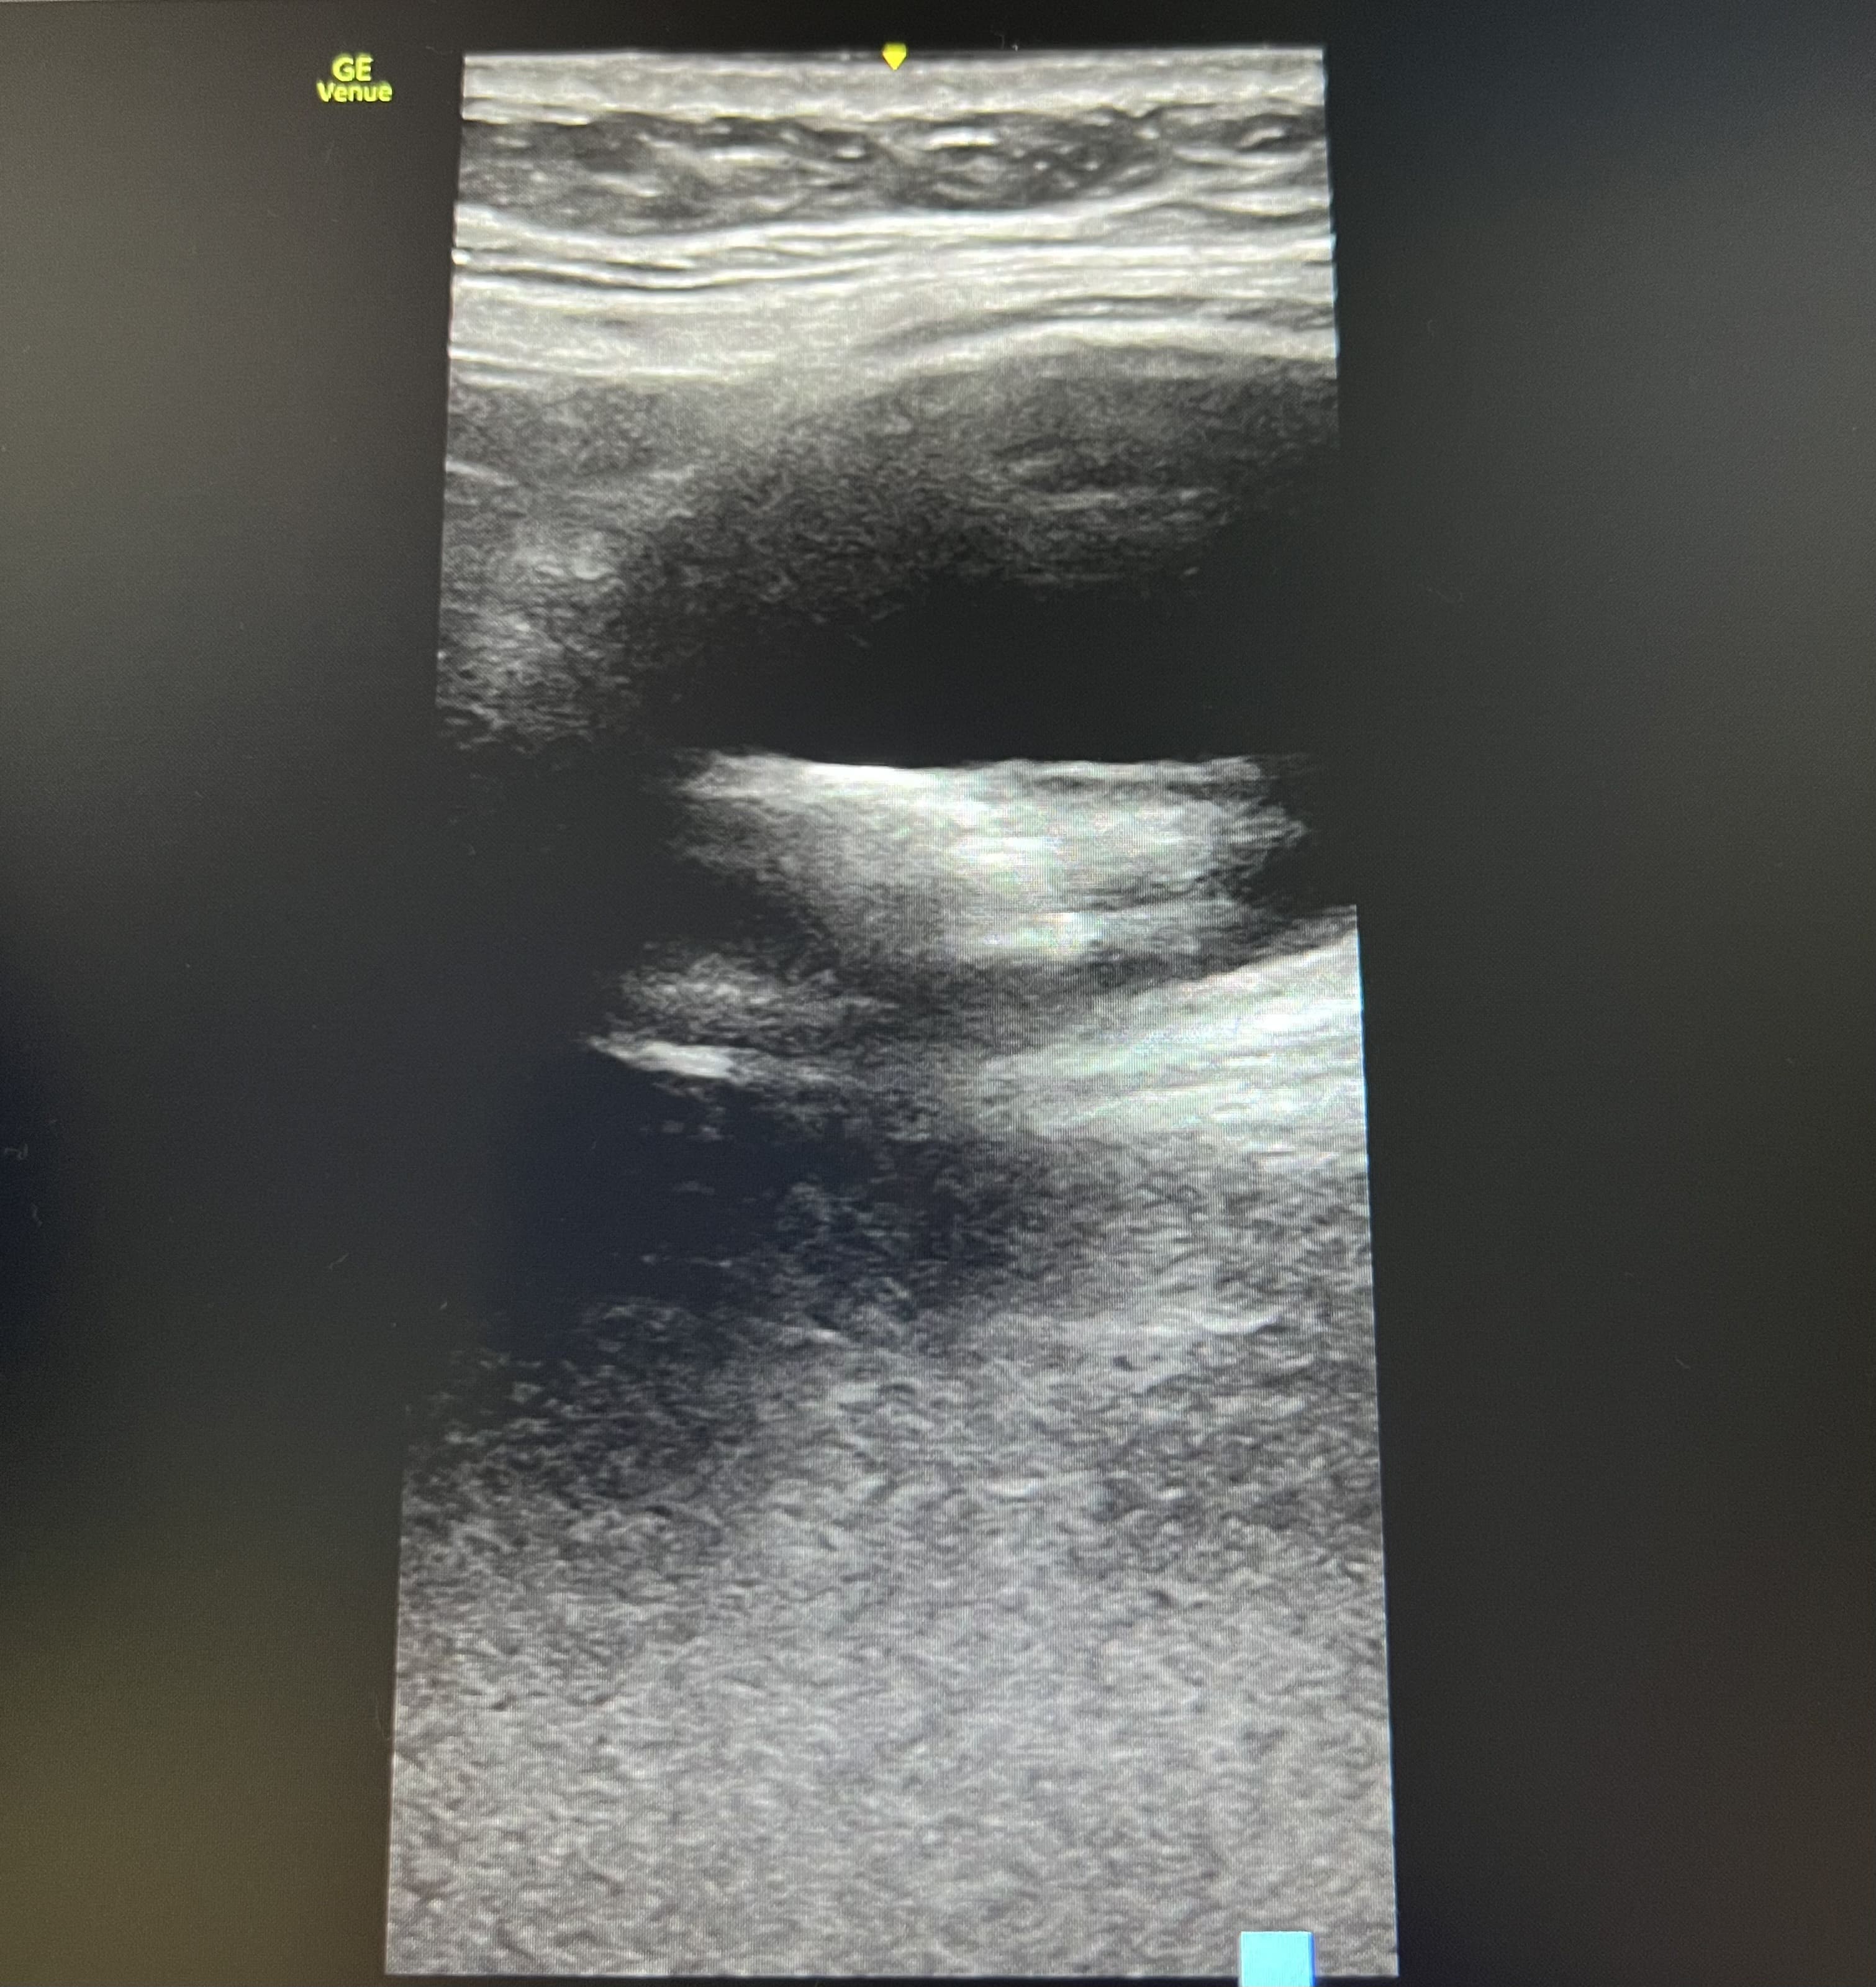

Pruebas complementarias: Ecografía abdominal con sonda convexa: vesícula biliar distendida con litiasis de 4 centímetros en su interior y sombra acústica posterior. Ecografía con sonda lineal en flanco derecho: lesión anecoica ovalada con imagen hiperecoica en su interior, que no captan Doppler, y movilizan con la respiración, en tejido subcutáneo.